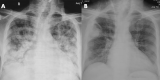

Severe coronavirus disease (COVID-19) is currently managed with systemic glucocorticoids. Opportunistic fungal infections are of concern in such patients. While COVID-19 associated pulmonary aspergillosis is increasingly recognized, mucormycosis is rare. We describe a case of probable pulmonary mucormycosis in a 55-year-old man with diabetes, end-stage kidney disease, and COVID-19. The index case was diagnosed with pulmonary mucormycosis 21 days following admission for severe COVID-19. He received 5 g of liposomal amphotericin B and was discharged after 54 days from the hospital. We also performed a systematic review of the literature and identified seven additional cases of COVID-19 associated mucormycosis (CAM). Of the eight cases included in our review, diabetes mellitus was the most common risk factor. Three subjects had no risk factor other than glucocorticoids for COVID-19. Mucormycosis usually developed 10-14 days after hospitalization. All except the index case died. In two subjects, CAM was diagnosed postmortem. Mucormycosis is an uncommon but serious infection that complicates the course of severe COVID-19. Subjects with diabetes mellitus and multiple risk factors may be at a higher risk for developing mucormycosis. Concurrent glucocorticoid therapy probably heightens the risk of mucormycosis. A high index of suspicion and aggressive management is required to improve outcomes.